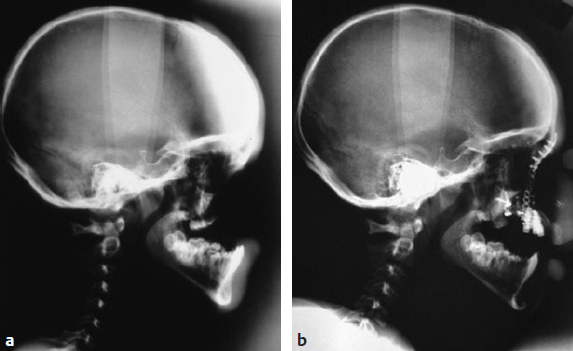

CHAPTER Modern plastic surgery concepts are based on the paradigm that plastic surgery must restore function as well as anatomy in all cases, regardless of the indication for surgery. In the case of facial plastic surgery, respecting the facial proportions is an elementary prerequisite for achieving an aesthetic reconstruction.1 The facial skeleton is a lightweight, mechanically stable structure that contains pneumatized cavities, houses organ systems, and allows for the fixation of the facial soft tissue envelope in a way that maintains musculoskeletal balance. In the case of loss or aplasia of facial parts, facial disfigurement increases in parallel with the extent of the maxillofacial defect. In this situation, ignoring the functional anatomy during the reconstruction effort invariably results in unsatisfactory outcomes. Since the introduction of microsurgical flap transfer, other methods of regenerative plastic surgery involving the induction of bone and soft tissues in surgical protocols with advanced block-grafting techniques, including prefabricated composite grafts and distraction osteogenesis and histogenesis, have been introduced and can help avoid unfavorable results in patients with severe maxillofacial defects. The bone–muscle crosstalk, which is associated with the regenerative plastic surgery methods mentioned earlier, has beneficial clinical effects on the musculoskeletal balance of the face and is useful for achieving a full rehabilitation. Restorative plastic surgery requires the simultaneous reconstruction of maxillofacial aesthetics and function in all cases, regardless of the indication for surgery, and relies on the surgical concept of like-with-like reconstruction combined with the skeletal rearrangement of the disfigured face. By considering aesthetics and function as an inseparable unit during the induction of functional tissues, the historical separation between plastic reconstructive and aesthetic surgery has been broken. Summary Box Complications in Maxillofacial Reconstruction • Absence of physiologic mucosal lining and gingiva • Facial deformity • Need for repeat bone grafts • Oral mobility loss • Implant loss • Excessive mucous secretion • Persistent peristalsis • Maceration • Hair growth The face is involved in speaking, mastication, deglutition, and effortless breathing, and these functions dictate the main objective of any facial treatment: to restore physiological function. The reconstruction of the face, a pneumatized, lightweight, mechanically stable structure to which the facial soft tissue envelope is fixed to maintain musculoskeletal balance, has proven to be a surgical challenge. Fig. 50.1 (a) An unfavorable result caused by intraoral bulkiness in a 58-year-old woman after hemimaxillectomy and reconstruction with an osseomyocutaneous flap. (b) An unfavorable result caused by extraoral “sinus bulkiness” in a 27-year-old patient with loss of the maxilla after tumor surgery and postoperative radiotherapy. Combination of prefabricated scapular flap and obturation of the sinus with a teres major flap. (c) An unfavorable result caused by “bony bulkiness” in a 57-year-old patient after microsurgical reconstruction of the mandible, tongue, and mouth floor with an iliac prefabricated composite graft and external oblique muscle free flap, first described in 1997. (a From Zimpfer M. Department of Anesthesiology and General Intensive Care University of Vienna 1996–2000 Patient Care–Teaching–Research, self-published; b,c from Holle J, Vinzenz K, Würinger E, Kulenkampff KJ, Saidi M. The prefabricated combined scapula flap for bony and soft-tissue reconstruction in maxillofacial defects—a new method. Plast Reconstr Surg 1996;98(3):542–552.) Among the established core principles of craniofacial surgery including “safe approaches, careful designed osteotomies and rigid skeletal fixation”2; advanced bone grafting techniques using the induction of specialized hard and soft tissues in the reconstruction effort are part of the trendsetting advances in regenerative plastic surgery.2 Vascularized osseous, osseocutaneous and myocutaneous free flaps, preferably taken from the fibula, scapula or iliac crest, are standard techniques in facial plastic surgery today.3 The techniques of soft tissue flaps and the microsurgical revascularization of transplants in the maxillofacial area, on the other hand, have not changed significantly since their introduction and are not discussed further here. From a functional point of view, the shortcomings of the use of the current standard free flap methods in facial plastic surgery are as follows: • Closure in severe defects with myocutaneous flaps, irrespective of dermal texture4 • Obturation of pneumatized cavities6 • Reconstruction of a bony framework rather than restoration of the anatomy7 In addition, the current free flap methods occasionally result in bulkiness, which prevents the satisfactory restoration of aesthetics and function5–7 (Fig. 50.1). Stepwise adaptations and corrections can help to achieve acceptable clinical outcomes, but only in the case of mandibular reconstructions6 (Fig. 50.2). Fig. 50.2 Stepwise aesthetic and functional rehabilitation by trimming bulky flaps and integrating implant restoration. (From Holle J, Vinzenz K, Würinger E, Kulenkampff KJ, Saidi M. The prefabricated combined scapula flap for bony and soft-tissue reconstruction in maxillofacial defects—a new method. Plast Reconstr 1996;98(3):542-552.) For the reconstruction of a pneumatized midface, these free flap techniques are inappropriate, which has led to the trend of patient-specific implants and full-face transplantation.8–10 There is a flowing transition between tissue deficiency and defect, and if these persist long enough, they are usually combined with facial disfigurement; therefore complex surgical protocols, rather than simple free flap techniques, are necessary to avoid unfavorable results. The surgical concept of like-with-like restoration in the case of the oral and maxillofacial anatomy includes both the reconstruction of missing tissues and the rearrangement of the skeletal architecture of the face to achieve acceptable aesthetic and functional results, which can be best illustrated in cleft patients. Two aspects must be taken into account during the treatment of maxillofacial deficiencies or defects: 1. Like-with-like reconstruction based on the three “identities,” namely, identical size, identical shape, and identical tissue structure to those of the recipient site.6,11,12 2. Correction of facial disfigurement using grafts and/or surgical orthognathic procedures.13,14 Depending on the extent of the tissue deficiency, a series of surgical methods have been described for different indications in maxillofacial surgery: • Osteoplastic reconstruction (e.g., “stack plasty”) of the alveolus and osteoplasty of tertiary clefts14 • Prefabrication and prelamination of osseous grafts for the reconstruction of large alveolar defects15 • Complex prefabricated grafts for microsurgical reconstruction of the maxilla and midface6,12,16,17 From the point of view of functional anatomy, there are four problems that need to be overcome: 1. Reconstruction of a pneumatized, lightweight skeletal structure with mechanical stability 2. Establishment of a stable inner lining of cavities 3. Establishment of gingiva that is resistant to masticatory loading 4. Prevention of graft inflammation, especially at the implant site Before the development of prefabricated composite grafts, the inner lining of the oral cavity was reconstructed using full- or split-thickness skin grafts, intestinal grafts, and mucosal grafts.4,18,19 However, hair growth, maceration, persistent peristalsis, and excessive mucous secretion have diminished the acceptability of these grafts for the replacement of the oral lining. Furthermore, a high rate of implant loss was observed with these grafts because of deep and persistently inflamed pockets around the site where the dental implant penetrated the gingiva. Moreover, attempts at reconstruction with mucosal prelamination of fasciocutaneous flaps failed because of severe scarring of the lining combined with further loss of oral mobility, particularly in the case of reconstructions of the floor of the mouth.18 Fig. 50.3 The surgical procedure for prefabricating composite flaps from the scapula (a) and iliac crest (b). PTFE, Polytetrafluoroethylene. Fig. 50.4 Reconstruction of the mandible with a prefabricated iliac composite graft with a periodontal unit consisting of the bony alveolus, gingiva, and implant restoration in a 57-year-old man who had undergone mandibulectomy. (Reproduced from Vinzenz K, Schaudy C. Osteoplastic surgery of the face—state of the art and future aspects. Eur Surg 2011;43(5):270-283, with permission from Springer-Verlag Wien.) Dermal prelamination of the bone, which was first cited in 1996,6,12 is a complex prefabricated composite graft that allows the restoration of the pneumatized, lightweight skeletal architecture of the face by replacing like with like.6,12,16 As illustrated in Fig. 50.3, the prefabrication of complex composite grafts includes the following: • Preformation of the bony graft • Dermal prelamination of the bony graft • Installation of dental implants The transplant is enveloped in an expanded polytetrafluoroethylene (ePTFE) membrane and allowed to mature at the donor site for several months. After maturation, a graft with a “perfect fit” can be harvested and used for reconstruction. Prefabricated grafts from the scapula are best suited to midface reconstructions, whereas those from the iliac crest are best suited to mandibular reconstructions (see Fig. 50.3) Revascularization is only required for transplants exceeding 4 cm in diameter (Video 50.1).20 A prerequisite for the use of prefabricated grafts is concept surgery, which is defined as surgery that follows a predefined objective and a detailed, preoperatively prepared, stepwise plan, as opposed to routine surgery, which does not involve or strictly follow such plans and may involve a wide variety of perioperative protocols with unknown effects on the surgical outcome.21 Concept surgery requires12,22,23: • A clear definition of the aspired clinical result • Computer-assisted operation planning to transform the surgical concept into clinical reality • Accurate postoperative control using computer-assisted design systems • Critical scientific analysis of the clinical results If these criteria are not met or if a multistage surgery is required at the recipient site, the clinical effort of transplant prefabrication and the physical as well as psychological stress to the patient are difficult to justify.18,24–28 Most of the cited surgical protocols for graft prefabrication have been abandoned because of unfavorable results and complications. Essential in orofacial reconstruction is the prefabrication of an artificial periodontal unit, consisting of the alveolar bone, gingiva, and dental implants, as an integrated component of the entire graft (Fig. 50.4). Thus full oral function is available immediately after the completion of dental restoration.13 Only by inflammation-free periointegration of the dental implants will the implant site be sealed against the oral environment, allowing a stable and successful long-term result.22,23,29 While the alveolar crest of the maxilla can be restored using block-graft techniques,14,15 the pneumatized skeletal anatomy of the midface should preferably be reconstructed using prefabricated composite grafts6 (Fig. 50.5). Midface defects affect all tissue structures and require treatment before disfigurement is caused by the tendency of the tissues to close the defects by shrinking. Fig. 50.5 (a) Three-dimensional computed tomography after surgery to verify the correct fit of a prefabricated composite graft. Note in particular the exact intersection at the palate. (b) Reconstruction of the maxillary sinus as a pneumatized paranasal cavity. (c) Reconstruction of the alveolus and palate in the second quadrant with an attached masticatory gingiva and integrated implant restoration at 6 weeks postoperatively. (From Holle J, Vinzenz K, Würinger E, Kulenkampff KJ, Saidi M. The prefabricated combined scapula flap for bony and soft-tissue reconstruction in maxillofacial defects—a new method. Plast Reconstr Surg 1996;98(3):542–552.) Furthermore, the graft must fit perfectly into the defect (“click in place”), which can be achieved using accurate preoperative computer-assisted planning.12,13,16,17 In complex midface reconstruction, the prefabricated graft is “suspended” into the defect using osteosynthesis titanium miniplates connected to already-osseointegrated dental implants17 (Figs. 50.6 and 50.7) This new method ensures fast restoration of oral function, pneumatized nasal and paranasal cavities, and high graft stability for several years. Therefore this method is preferred in diseases with severe scarring, such as noma.17 Regenerative medicine is the “process of replacing, engineering or regenerating human cells, tissues or organs to restore or establish normal function via stimulating the body’s own repair mechanisms.”30 McCarthy et al,31 who established distraction osteogenesis in maxillofacial surgery before the turn of the millennium, were the first to take craniofacial surgery out of the field of soft tissue and bony reconstructions and into that of tissue engineering and “inductive surgery.” Shortly thereafter, the first scientific studies on tissue induction in prefabricated composite grafts were published.22,23 The main novelty of this procedure is the placement of a dermal graft over the bone to create a substitute for the oral mucosa and avoid the unfavorable results obtained with skin and intestinal grafts. A stable attachment to the bone is essential for the restoration of the inner oral lining (Fig. 50.8). Histomorphologic evaluation of prefabricated composite grafts has shown that the dermis is attached in a periosteum-like manner to the extensively remodeled bone, which osseointegrates the inserted titanium implants, and that the basal parts of the dermis are attached to a papillary connective tissue layer.12 Fig. 50.6 (a–c) An osteosynthesis plate is attached to additional dental implants (yellow arrows) in the graft, and the graft is suspended in the defect (clicked in place). (c From Vinzenz K, Holle J, Würinger E. Reconstruction of the maxilla with prefabricated scapular flaps in noma patients. Plast Reconstr Surg 2008;121(6):1964–1973.) Fig. 50.7 Lateral radiographic studies before (a) and after (b) reconstruction of the entire midface, including the maxilla, palate, and nose, in a patient with severe noma. (From Vinzenz K, Holle J, Würinger E. Reconstruction of the maxilla with prefabricated scapular flaps in noma patients. Plast Reconstr Surg 2008;121(6):1964–1973.) Fig. 50.8 Characteristics of a prefabricated composite graft. (1) Remodeling activity of the bone. (2) An osseomucosal unit with periosteum-like attachment of the lining. (3) Epithelium fixed to the underlying connective tissue by rete ridges. (Reproduced from Vinzenz K, Schaudy C. Osteoplastic surgery of the face–state of the art and future aspects. Eur Surg 2011;43(5):270–283, with permission from Springer-Verlag Wien.) The quality of the epithelium of the inducted bone and the attached lining can be ascertained via immunohistochemical analysis. Most importantly, the prefabricated grafts are covered by an almost normal epithelium within 4 weeks after flap transfer. The epithelium is fixed to the underlining connective tissue by rete ridges. The observation of keratin expression by the epithelial cells indicates a clinically verified complete restitution of the mucosa.23 Because a prefabricated composite graft consists of bone and dental implants, it provides an excellent surface for the development of a keratinized, attached epithelium that withstands masticatory forces because of the increasing number and size of the connective tissue parts within it after the reconstruction surgery. The attached epithelium resembles the normal mucosa and seals the implants against the oral environment.22,29 The mucosal covering becomes rapidly populated by dendritic cells, which are major players in the initiation of specific immune responses, and this may additionally contribute to a low periimplant infection rate.22 In both reconstructive and aesthetic surgery, the facial proportions represent the gold standard of aesthetic appearance1 (Fig. 50.9, Video 50.2). Distraction osteogenesis is an inductive surgery that combines reconstructive surgery with aesthetic surgery of the face, depending on the distraction distance. In distraction osteogenesis, the gradual advancement of a bone segment leads to the formation of new bone behind it, and distraction histogenesis is the biologic process of soft tissue adaptation to the resultant gradual stretching.32 Bone transport represents an alternative to microsurgical midface reconstruction. Similar to prefabricated composite grafts, this method provides a new lining via expansion of the attached gingival tissue, which aids in the periointegration of dental implants and resists functional loading during mastication.29 In orthognathic surgery, distraction osteogenesis is best suited for the three-dimensional rearrangement of the face to optimize the facial proportions in various indications, including complex surgical protocols such as those in cleft surgery. Moreover, the muscles adherent to the distracted bone are stimulated to create new cells at the origins and insertions of the muscles as well as within the muscle mass. In addition, the bone–muscle crosstalk, which is the interaction between the regenerating muscles and the remodeling bone, improves the musculoskeletal balance of the face, leading to a better aesthetic appearance, as shown in a 28-year-old patient who had undergone unsuccessful orthognathic treatment for 7 years (Fig. 50.10). However, it must be noted that bone transport related to distraction osteogenesis across large distances may cause injury of the skeletal muscles.33 Based on the principles described previously, bone transport can be used as an alternative to microsurgical reconstruction using prefabricated composite grafts in patients with noma (see Fig. 50.9, 7). The main advantages in this setting are the requirement of fewer and cheaper surgical instruments, the shorter operation time, and the lack of a need for admission into an intensive care unit, which makes this technique applicable in developing countries, for instance, in Africa.13,17 Fig. 50.9 Possible osteotomies and regions of distraction osteogenesis (DO), with various indications for distraction in the maxillofacial region. (1) Advancement of the entire face, mostly used in syndromic patients. (2) Midface distraction in high Le Fort II or Le Fort III osteotomy. (3 and 5) Distraction of an alveolar bone block to increase the height of the alveolus. (4) Lengthening of the mandible in the sagittal dimension. (6) Distraction of the ascending branch of the mandible. (7) Bone transport. The schema should further illustrate the facial soft tissue envelope being supported by the underlying bone structure of the face. This functional musculoskeletal interaction, the “bone–muscle crosstalk,” in the face is best described as sectorial architectonic shoring (see Fig. 50.11). Fig. 50.10 Managing unfavorable results. This 28-year-old patient was treated with a comprehensive orthognathic surgical protocol including distraction osteogenesis after failure of orthodontic treatment for 7 years. (a) Disrupted facial proportions, tension on the facial soft tissue envelope with pronounced nasolabial and mentolabial folds, and “chubby cheeks” caused by displaced retaining ligaments and a loss of the alveolar bone in the piriform region and lateral maxillary segments. (b) Aesthetic appearance after skeletal rearrangement with bimaxillary orthognathic surgery including distraction osteogenesis, maxillary reconstruction by stack plasty, and restoration of musculoskeletal balance. (Reproduced from Vinzenz K, Schaudy C. Osteoplastic surgery of the face–state of the art and future aspects. Eur Surg 2011;43(5):270–283, with permission from Springer-Verlag Wien.) Fig. 50.11 Olympic Stadium, Munich (by architect Frei Otto), as an example of sectorial architectonic shoring. (2014 M(e)ister Eiskalt—Picture used under Creative Commons License.) Distraction osteogenesis has three major advantages over conventional orthognathic surgery: 1. It is possible to move segments over a longer distance, thereby reducing the need for further bone grafts. 2. It provides stable, long-term outcomes. 3. It enables the three-dimensional rearrangement of the face in the case of facial disfigurement, especially in the transverse dimension, as is needed in cleft patients.6,13 For these reasons, distraction is useful in the complex surgical protocols of cleft surgery. Moreover, a close functional relationship between the bone and soft tissue facial envelope can be achieved using distraction osteogenesis. The superficial facial fascia is cranially elongated in the neck and has deep attachments in the temporal and periorbital regions.34 This surgical anatomy of the fascia is the key to understanding the functional changes in the aesthetic appearance of the face during distraction osteogenesis. In the fat compartments of the face, the deep and superficial fascial planes are separated by areolar tissue that is adherent to both planes through a series of dense fibrous attachments.35 The fascia with its viscoelastic properties is normally considered a passive structure that transmits mechanical tension generated by muscular activities.36 Advanced bone relocation surgery changes the tension on the fascia and the superficial musculoaponeurotic system (SMAS) via retaining ligaments, which function as sectorial architectonic shoring over the fat compartments (Fig. 50.11). As a consequence, this leads to greater primary tension on the SMAS and fixed mimic muscles.